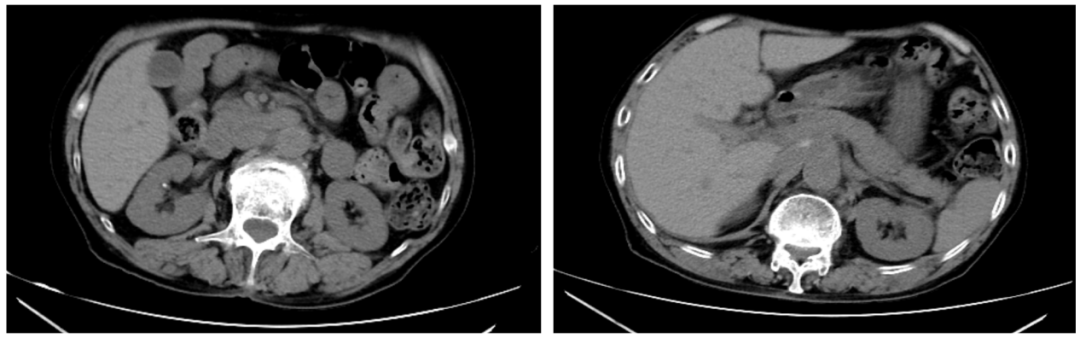

2025-08-30复查腹部及盆腔CT示:腹腔及腹膜后见多发软组织团块影,部分融合,边界不清,部分较前减小;左侧髂血管走行区及腹股沟区见多发稍大淋巴结影,较前变化不大。

2025-11-04,复查超声提示:左侧锁骨上见2-3个肿大淋巴结,大者0.9×0.6cm,结构欠清;左侧腋下见2-3个肿大淋巴结,大者1.0×0.5cm,皮质增厚,髓质偏心,左侧腹股沟区见1.5×0.4cm肿大淋巴结,均皮质稍增厚,髓质尚清。腹膜后未见明显有意义肿大淋巴结。综合CT等相关检查结果,提示疾病得到有效控制。

截至2025-12,匹妥布替尼单药治疗已有9个月,患者未再出现疾病的进展或复发,安全性良好,可耐受,目前仍在持续用药及随访中。

图3 匹妥布替尼治疗后患者腹部CT表现

本例老年高危DLBCL患者历经多线治疗仍反复复发,且对多种化疗药物耐受性差,治疗过程充满挑战。启用匹妥布替尼治疗后,患者未再出现腹痛等症状,影像学提示病灶稳定甚至部分缩小,治疗9个月以来病情持续控制,且未出现明显不良反应,体现出该药良好的疗效与耐受性。从机制上看,匹妥布替尼具有高选择性的布鲁顿酪氨酸激酶(BTK)抑制特性,激酶活性试验显示其在100 nM浓度下仅抑制4种激酶,对BTK的抑制率高达97%4。酶谱分析亦显示,匹妥布替尼对BTK的选择性比98%的其他人类激酶高300倍以上,降低了潜在的脱靶毒性5。此外,在肝功能不全患者中,匹妥布替尼未出现药时曲线下面积(AUC)升高,重度